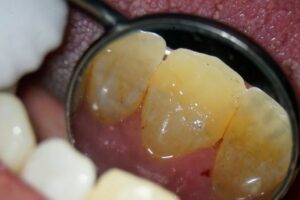

Der provisorische Aufbau erfolgte durch den Endodontologen mit vorab gefertigtem Silikonschlüssel mittels Tetric Flow und Ceram A3,5 als Abschluss der Single-Visit-Behandlung. Die endgültige Krone konnte am 12. Juni 2025 eingegliedert werden.

Insgesamt ist die dargestellte Lösung weniger invasiv und damit patientenorientierter. Eine alternative Extraktion mit Implantatversorgung wäre aufgrund des nötigen Weichgewebsmanagements deutlich anspruchsvoller gewesen, insbesondere aufgrund der bestehenden Vorerkrankung. Nach dem effektiven Verschluss des Wurzelkanals war eine sofortige Restauration möglich, was auch der Ästhetik dient.

Die Vorteile der aufgezeigten Behandlungsstrategie liegen nicht nur in der Risikominimierung für den Patienten, sondern auch in der nahtlosen Verzahnung mit der prothetischen Versorgung: ein Termin weniger, keine erneute Anästhesie, kein Risiko einer bakteriellen Rekontamination. Somit eine interdisziplinäre Therapie, die funktionell, restaurativ und ästhetisch überzeugt. Der Patient konnte in weniger als zwei Monaten vollständig ästhetisch versorgt werden.